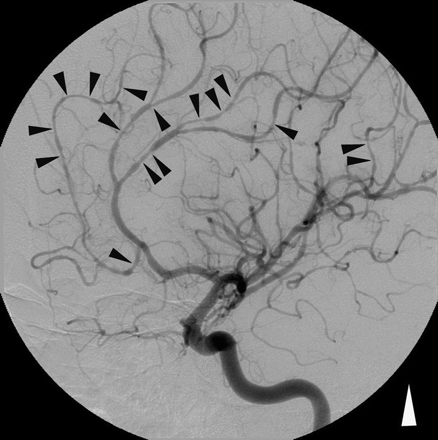

一个23岁的男人没有病史或物质滥用报告5攻击分散悸动的严重头痛三天时间内,每一个持续20分钟性交期间急性发作。

神经系统检查,CT、MRI和CSF分析显示没有异常。寻找动脉瘤,五天后出现头痛、血管造影显示分散执行多病灶的节段性大脑血管收缩的第二和第三顺序分支动脉环(在前,中间,和大脑后动脉,但不是动脉环本身)在没有动脉瘤(图)。

图。传统血管摄影显示多病灶的扩散前和大脑中动脉节段血管收缩。

这种血管造影模式(有或没有涉及动脉环)中可以看到特发性(即。在缺乏蛛网膜下腔出血)霹雳头痛。1、2血管痉挛的分布对比在孤立的中枢神经系统血管炎,血管痉挛总是限制在远端动脉直径小于0.5毫米。雷声头痛有或没有血管痉挛通常是因性行为,促使密集的努力,并发操作,急性高血压危象,或拟交感神经药物的摄入。这表明交感神经活动过度的可能性霹雳头痛。大脑动脉环和近端部分分支机构痛觉结构,这或许可以解释头痛伴随涉及这些血管的血管痉挛。